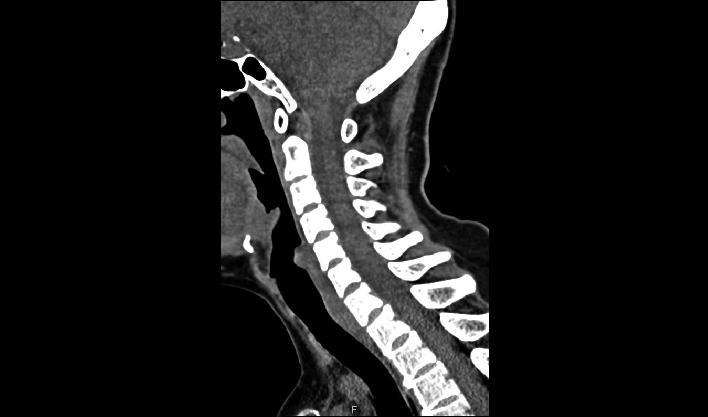

La matriz de reconstrucción de 1024*1024 amplía los datos de la imagen cuatro veces. Combinado con imágenes de corte fina, incluso las lesiones más invisibles son claramente visibles.